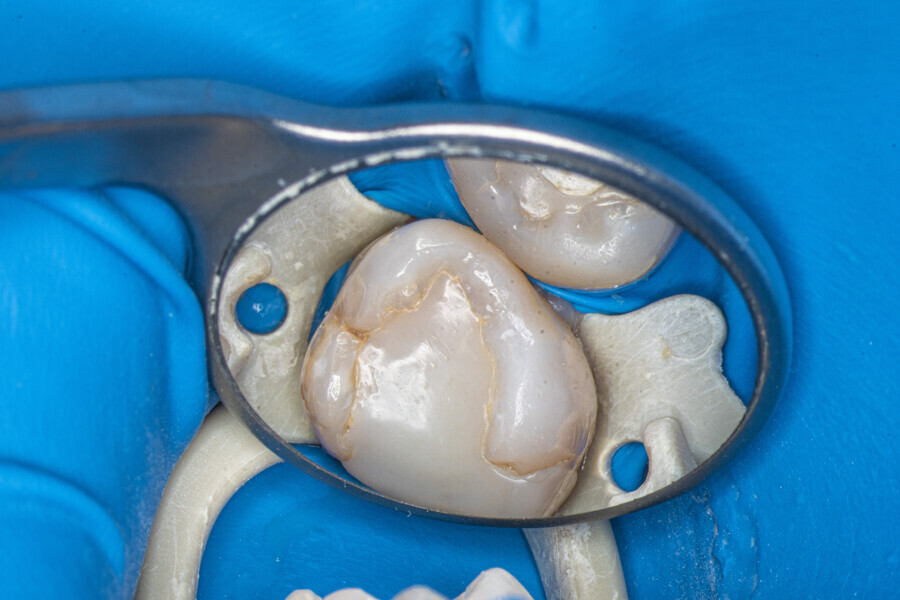

Case 2 (Figs. 27–36)

A 25-year-old female patient presented to the office owing to constant pain related to the mandibular left first molar. Pulp necrosis was diagnosed. After the emergency appointment, the patient was referred for complete treatment. The tooth was treated in the same manner as described in the previous paragraphs. After creation of the access cavity, the orifices were located. In the root chamber, the orifices of the MB, mesiolingual, DB, distomesial and distolingual canals were present. After pre-flaring and preparation of the middle third, the LPE enhanced irrigation protocol with the SkyPulse laser was performed. After the irrigation protocol in the mesial root, the irrigants started to flow between lingual and buccal canals. Such an observation suggested to the operator that some space in the isthmus had been created. It is worth mentioning that at this stage apical enlargement was not performed. Final preparation of all five canals was performed with the reciprocating file, and the final irrigation protocol was performed as in the previous case. The radiograph clearly revealed that the isthmus space was filled with the sealer. The radiograph and CBCT image revealed that there were four portals of exit in the mesial root.